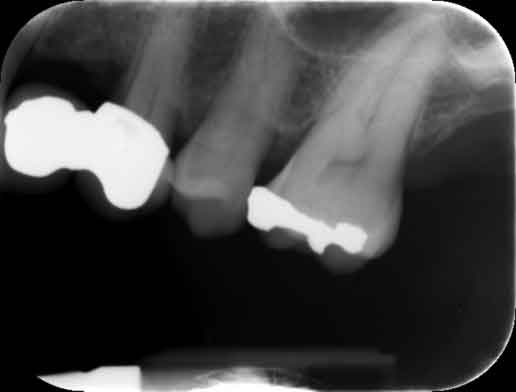

Return to "Modern Applications for The Cantilever Fixed Partial Denture" partial-denture-1 Next Previous